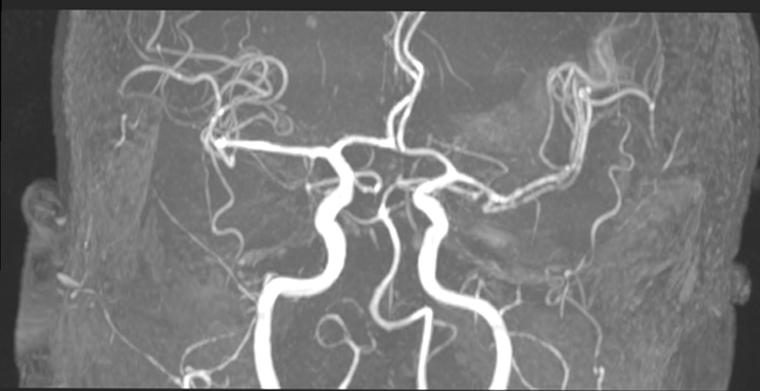

Anjiyo İşlemi Nedir?Anjiyo, tıbbi bir görüntüleme tekniği olan anjiyografi işleminin bir parçasıdır. Bu işlem, damarların (arterler ve venler) içinde bulunan kan akışını değerlendirmek için kullanılır. Anjiyo, genellikle kalp hastalıkları, periferik damar hastalıkları ve diğer vasküler problemler için tanı koyma amacıyla uygulanır. İşlem sırasında, damar içine ince bir kateter yerleştirilerek, kontrast madde enjekte edilir. Bu sayede, X-ray, MRI veya CT gibi görüntüleme yöntemleriyle damarların durumu detaylı bir şekilde incelenebilir. Anjiyo İşlemi Nasıl Yapılır?Anjiyo işlemi genellikle aşağıdaki adımları içerir: